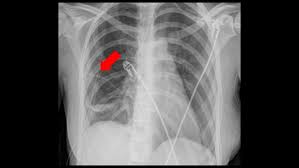

If you do have signs and symptoms, they may include: However, some residual scarring or damage may occur. Weak breathing (respiratory) muscles due to muscular dystrophy, spinal cord injury or another neuromuscular condition 8. Mucus plugs are also common in children, people with cystic fibrosis and during severe asthma attacks. Atelectasis, the collapse of part or all of a lung, is caused by a blockage of the air passages (bronchus or bronchioles) or by pressure on the lung. risk factors for atelectasis include anesthesia, prolonged bed rest with few changes in position, shallow breathing and underlying lung disease.